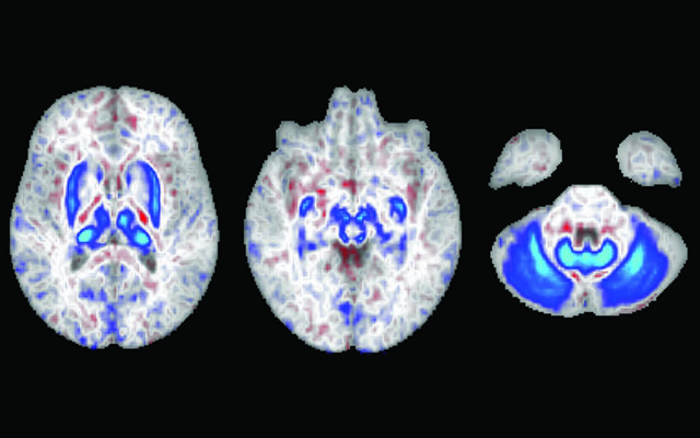

在这些脑部扫描中,蓝色区域表示有两个血色素沉着症风险基因的个体中铁积聚的区域。这些区域也在运动中发挥作用。

但在《JAMA Neurology》2022年8月1日在线版上发表的一项新研究中,加州大学圣地亚哥分校的研究人员与加州大学旧金山分校、约翰霍普金斯大学彭博公共卫生学院和Laureate大脑研究所的同事报告称,拥有两份基因突变副本(从父母双方各继承一份)的个体显示,大脑负责运动的区域有大量的铁积聚。研究结果表明,主要导致遗传性血色素沉着症的基因突变可能是导致运动障碍的危险因素,比如帕金森病,它是由产生化学信使多巴胺的神经细胞的缺失引起的。

根据美国疾病控制与预防中心(Centers for Disease Control and Prevention)的数据,这项观察性研究包括对836名参与者进行核磁共振扫描,其中165人有患上遗传性血色素沉着症的高风险,大约每300名非西班牙裔白人中就有1人患此病。扫描发现这些高危人群大脑运动回路中有大量铁沉积。然后,研究人员分析了近50万人的数据,发现血色素沉着症的遗传风险高的男性,而不是女性,患运动障碍的风险增加了1.8倍,其中许多人没有同时被诊断为血色素沉着症。